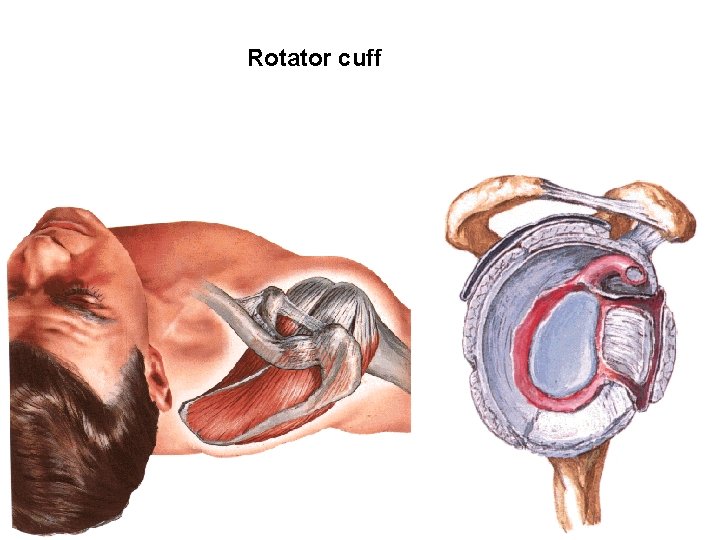

Rotator cuff